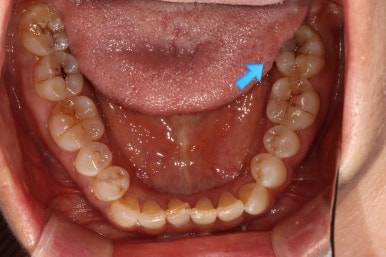

화살표로 가리치고 있는 치아의 불편감을 호소하고 계셨습니다.

보시다시피, 아래턱 큰어금니의 씹는면에 약간의 충치가 있는바.. 일단 레진으로 떼우기로 치료계획을 세웠었죠.

불편하다고 얘기하셔서 아까 파란색으로 표시했던 왼쪽 아래 어금니를 자세히 살펴보기 위해 치근단사진 촬영을 해보았습니다.

분명히 명확한 충치나 잇몸질환은 관찰되지 않았어요...